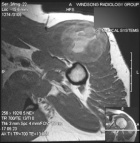

T.S. - 44 year old male with six month history of an anterior shoulder mass

Zoom image: Radiological image Radiological image.